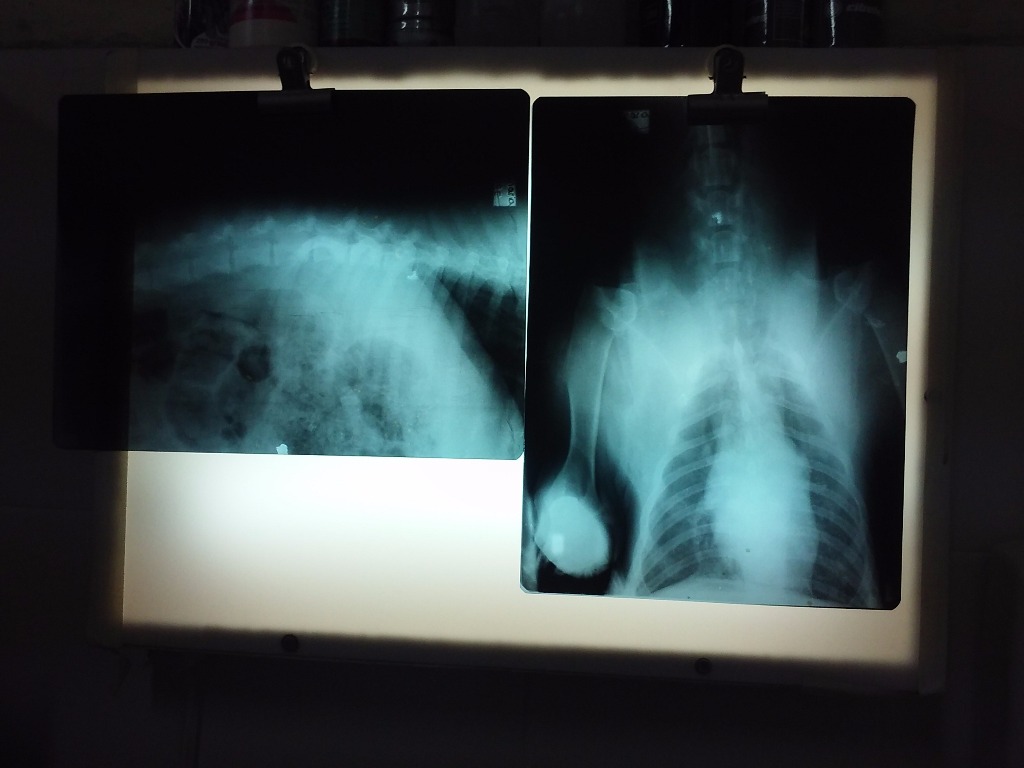

Nuestra veterinaria